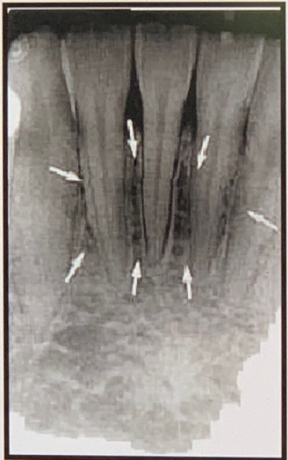

85. What is showing by arrow?

Genial Tubercles (Mental Spine) bony protuberances located on the lingual surface of the mandible slightly above the inferior border and in the midline. serve to attach the genioglossus muscles (at the superior tubercles) and the geniohyoid muscles (at the inferior tubercles) to the mandible. Usually well visualized on mandibular occlusal radiographs as one or more small projections.